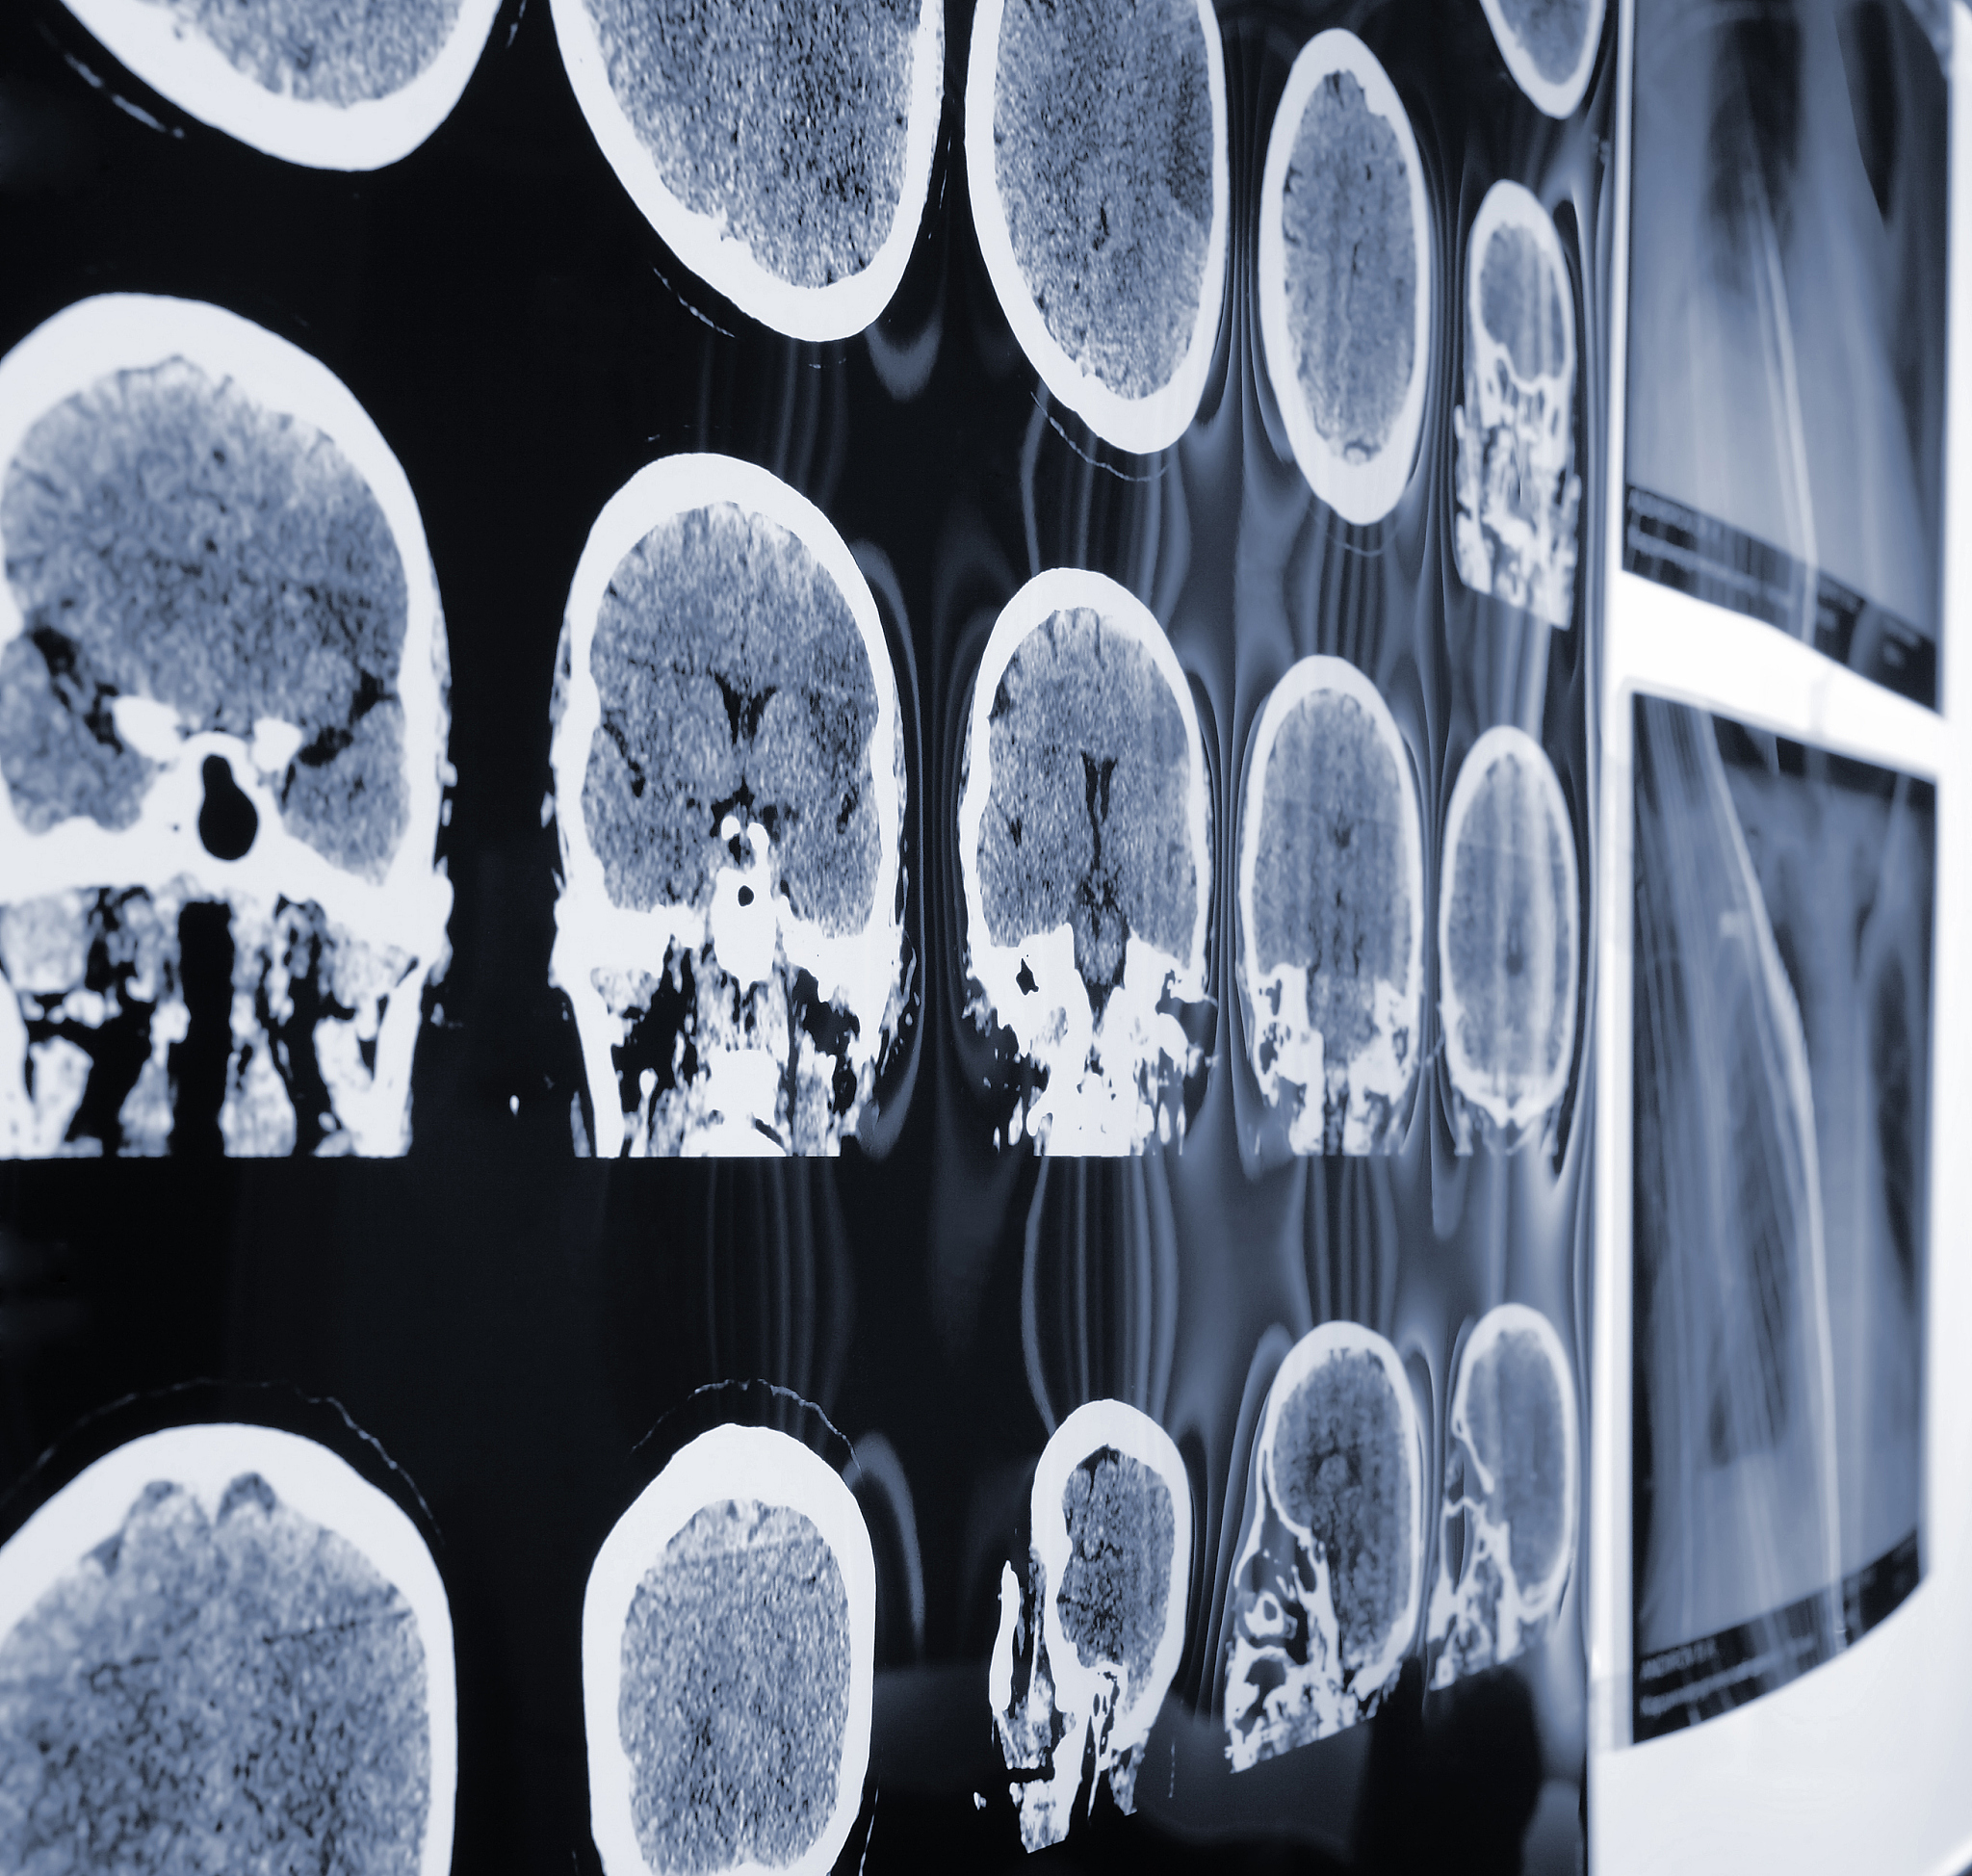

国际MICCAI Brainlesion Workshop是一个专注于脑病变研究的国际学术研讨会,由国际医学影像与计算机辅助诊断联合会(MICCAI)主办,致力于促进跨学科领域的交流和合作,推动脑病变的诊断、治疗和预防研究。该研讨会聚集了全球著名的生物医学工程师、影像学家、计算机科学家、神经学家、放射科医生等专家学者,共同探讨脑病变的最新研究成果、技术进展和临床应用,为推动脑病变研究和临床实践做出贡献。

MICCAI Brainlesion Workshop: 脑病变研究国际盛会